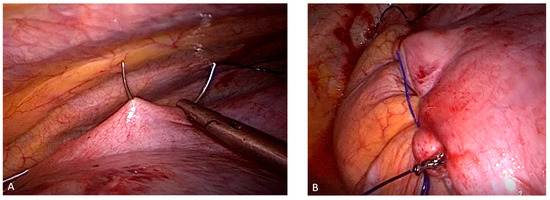

2.2. Surgical Procedure

| Type of sutures | 0.001 | ||

| One layer U-Sutures | 1 0.7 | ||

| One layer continuos suture | 9 | 7 | |

| Two layers (interrupted and running) 124 92 | 124 | 92 | |